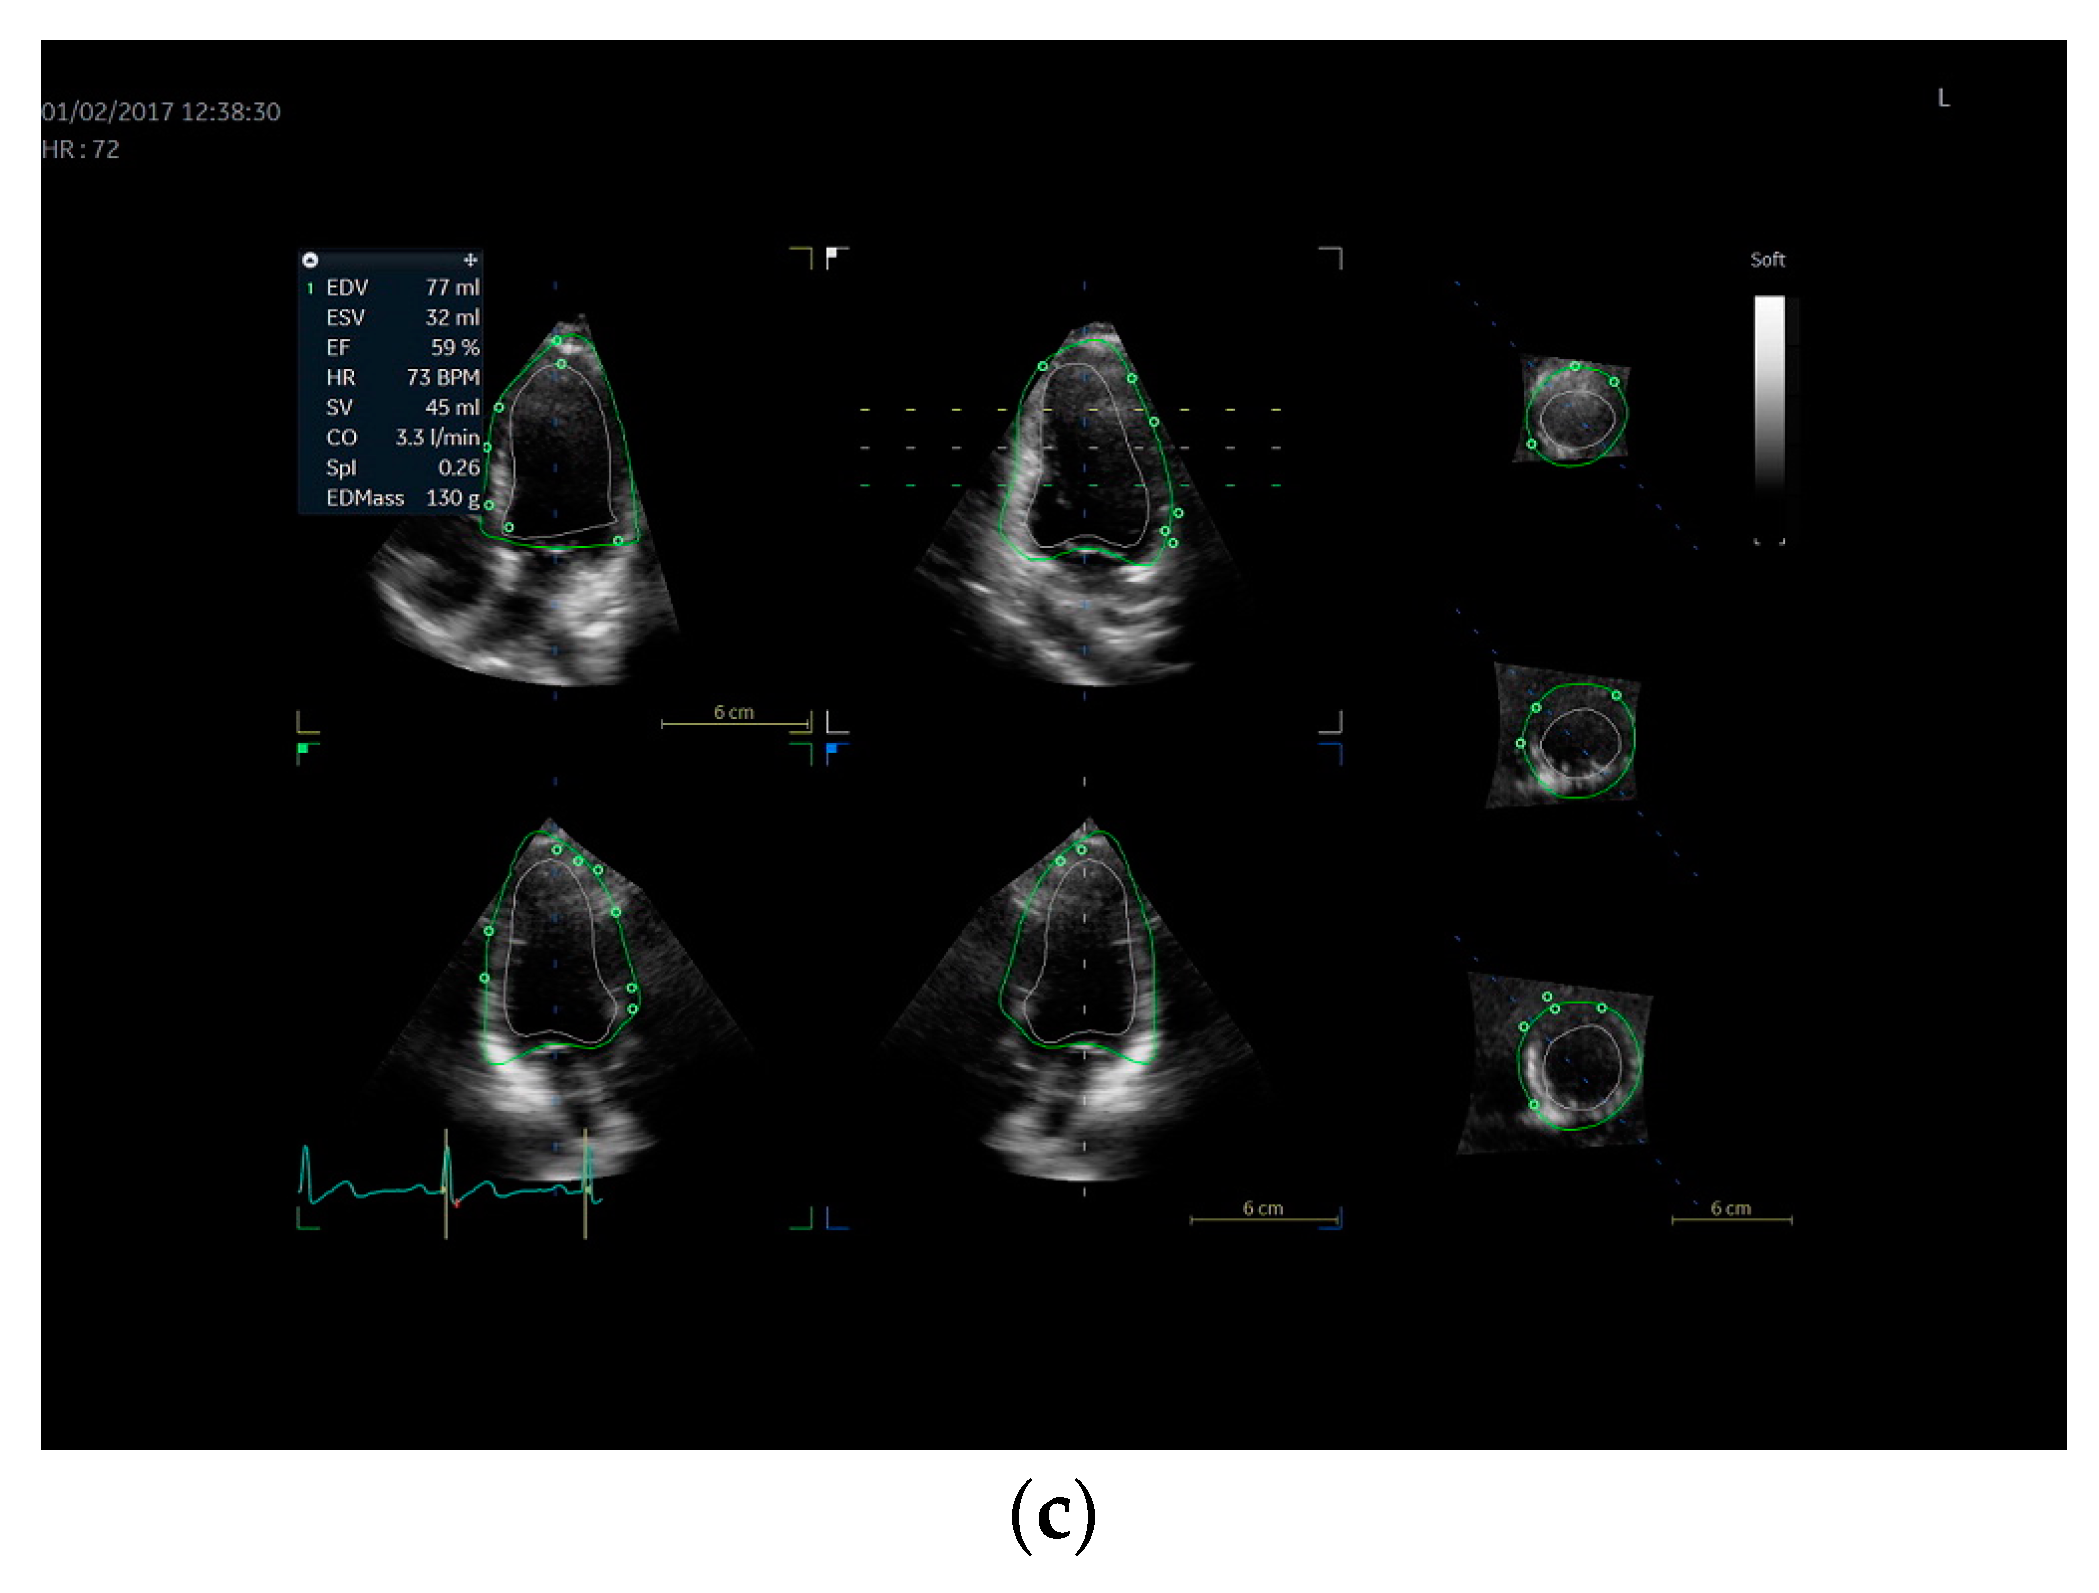

2.4. Echocardiography